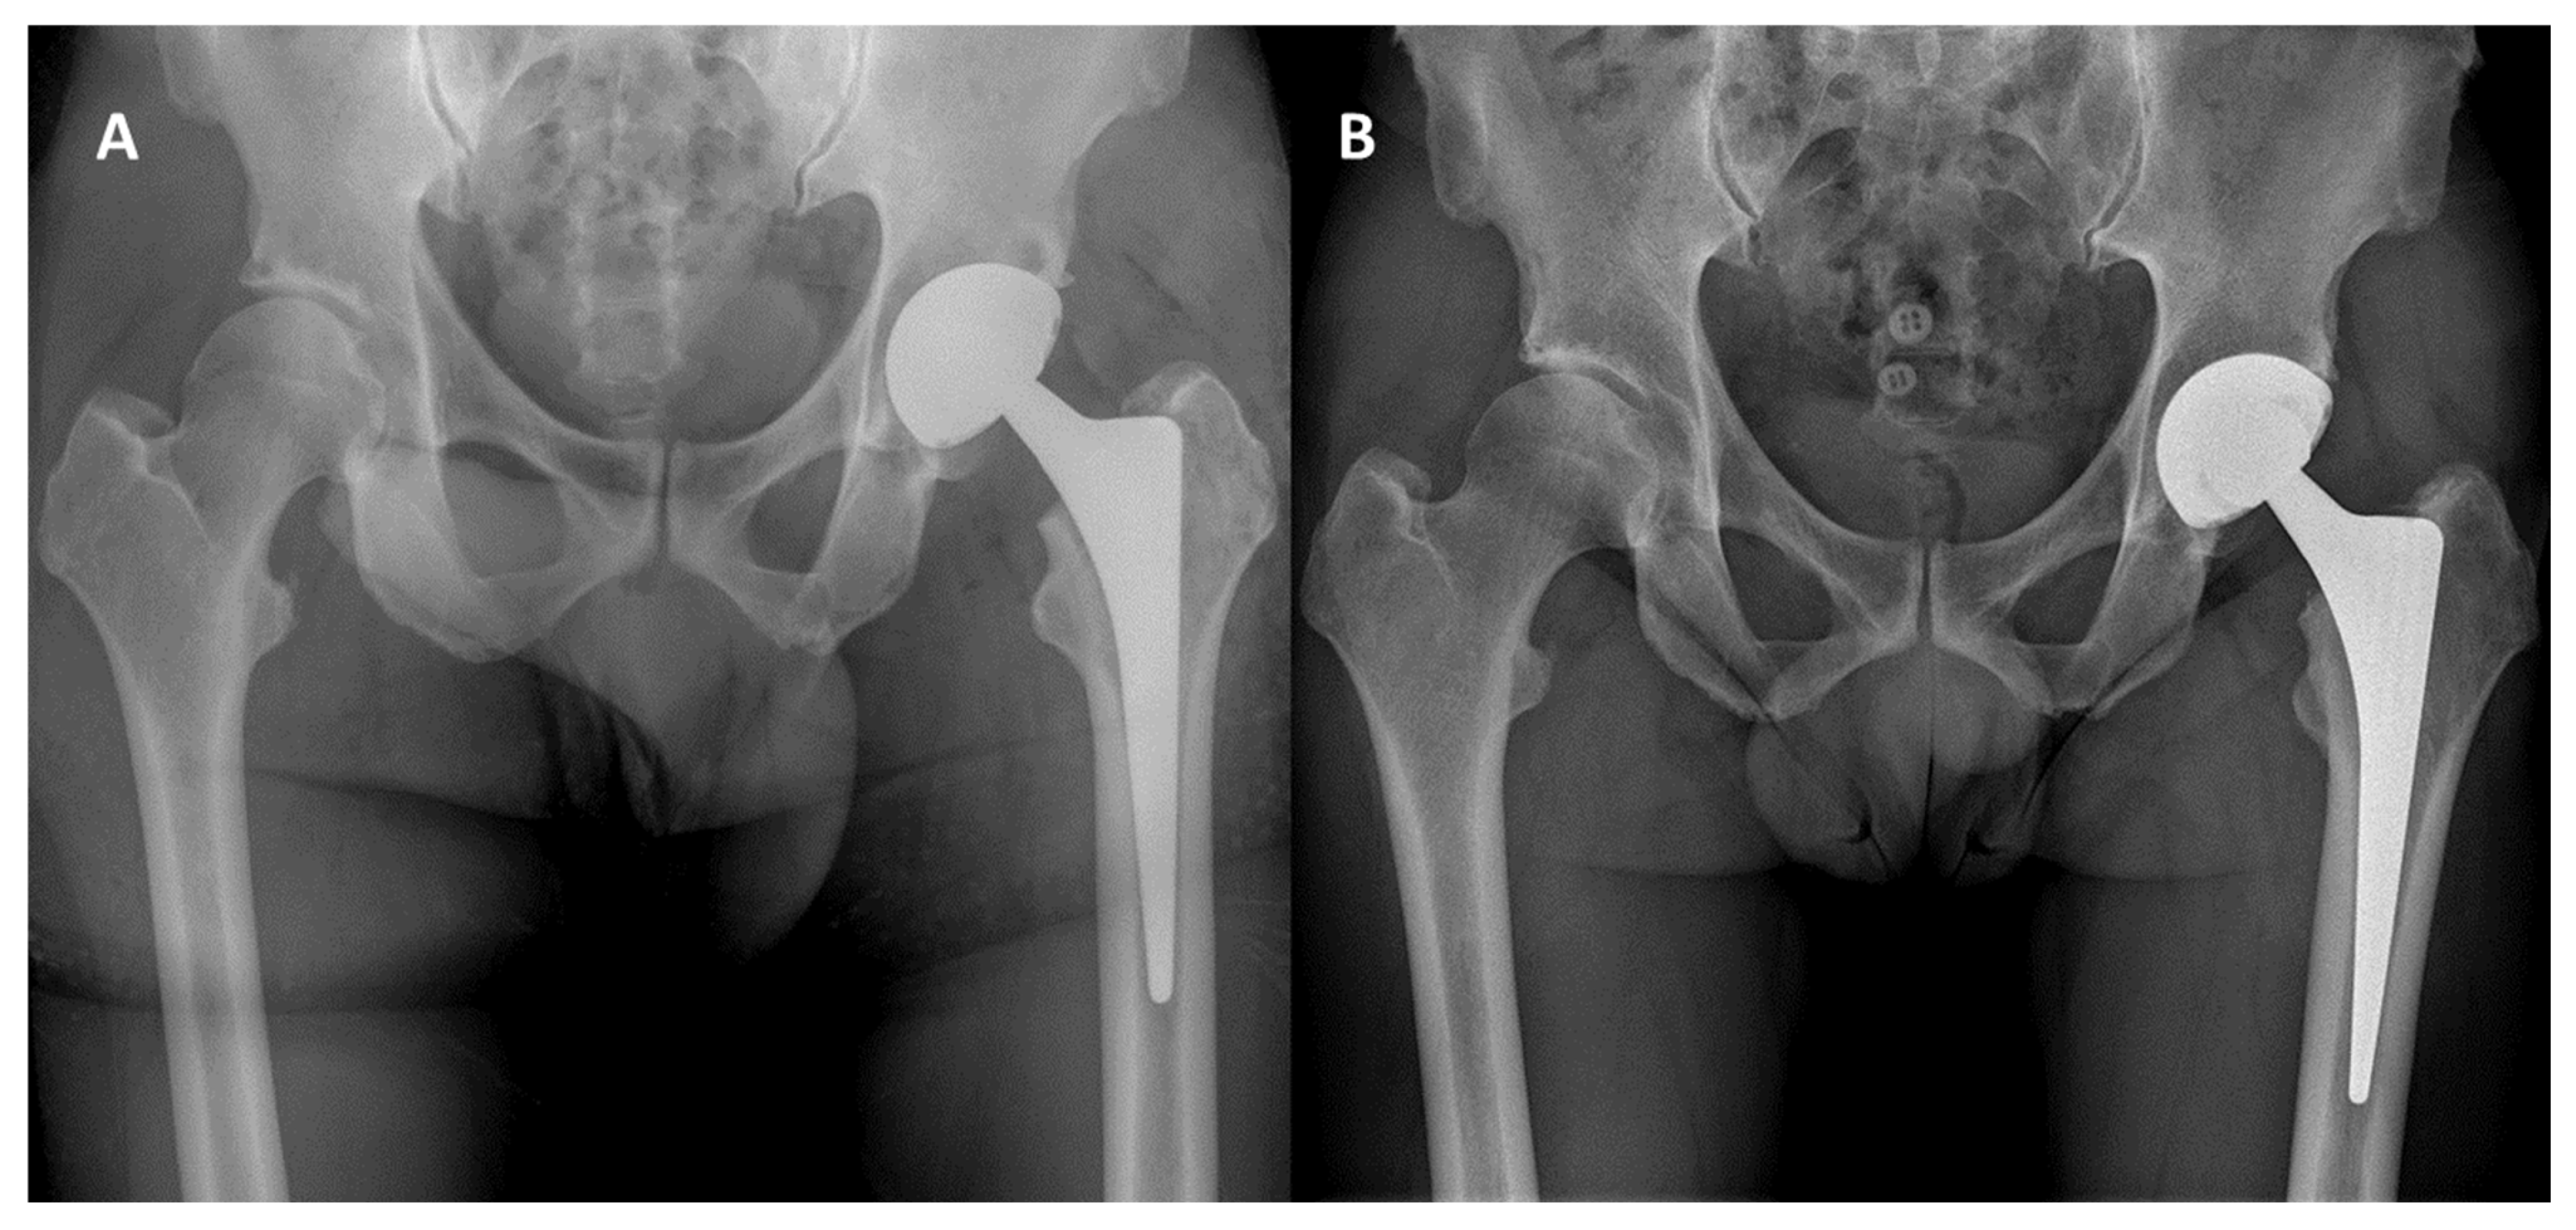

2.2. Surgical Procedure

3.3. Radiographic Outcomes